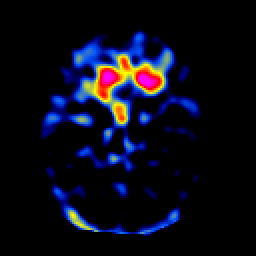

SPECT TL Study #3 -- Slice #20

[Home][Help][Clinical][Tour 1][Tour 2][Tour 3] Slice 20